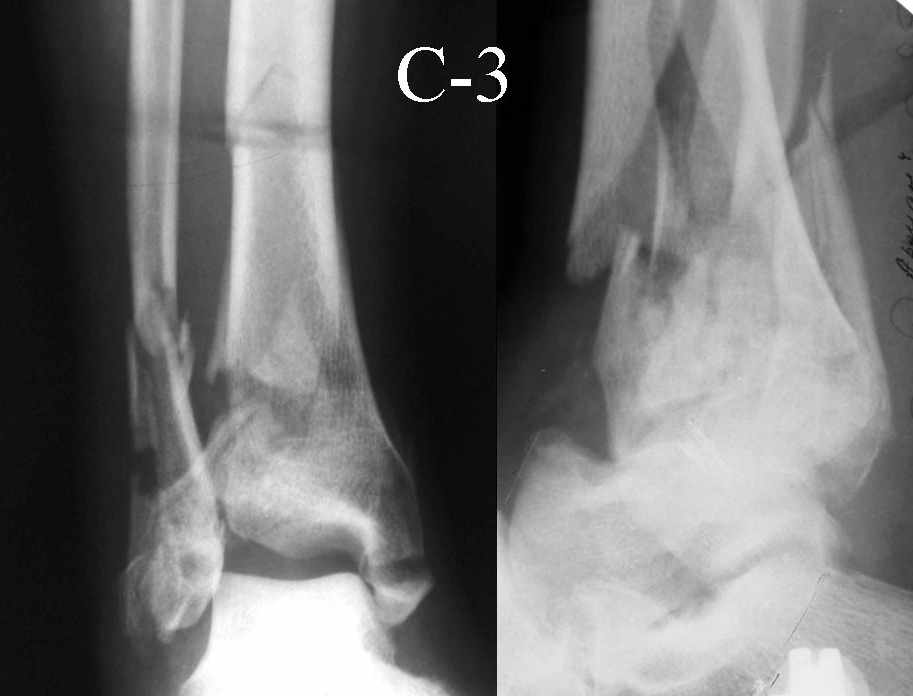

Это типичный перелом пилона, который надп лечить только открыто.Извини те что опоздал к обсуждению, но даже если вы уже оперировали больного по Илизарову это даже лучше.Посылаю картинки.

Дрягин

На рентгенограммах типичный перелом пилона по типу С-3. есть опыт до 100 открытых опреаций у нас в клинике. 20 примерно в год. Принцип один -все внутрисуставные переломы нуждаются в открытой репозиции и внутренней стабильной фиксации. При поступлении КТ не надо, так как получается только нагромождение костей. Истинной картины нет. Главное восстановить длину малоберцовой кости - это ключ к успеху. При поступлении меньше всего надо думать о сосудистых расстройствах, т.к. сама операция и репозиция даже сначала частичная даёт улучшение сосудитых нарушений. Причём очень быстро. Операция в 2этапа. При поступлении доступ позади наружной лодыжки, причём обязательно. После этого репозиция малоберцовой кости и фиксация пластиной 1/3 трубки под винт 3,5. Дренаж и любой аппарат наружной фиксации. Затем после спадения отёка на 5-7-10 день аппрат снимается и дугообразный разрез спереди от медиальной лодыжки 10-12 см. Главной чтобы расстояние между 1 и вторым разрезом было не меньше 7-8 см. Тогда не будет некрозов лоскутов. Таранная кость используется как матрица на неё укладываются отломки и фиксируются пицами. Ренг-контроль. Отломки лежат все отдельно, но ничего не высыпется. При переломах С-3 всегда нужна костная пластика (из крыла). Фиксация пластиной лист клевера простой или LCP. Гипс не нужен. Дренаж до 48 часов. Операция длится 3-4 часа обязательно без жгута. Посылаю примерно такой же случай.